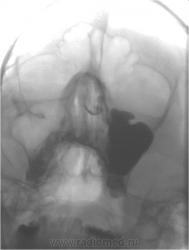

А, эти иллюстрации - опухолевый рост?

Это двухкамерная киста.